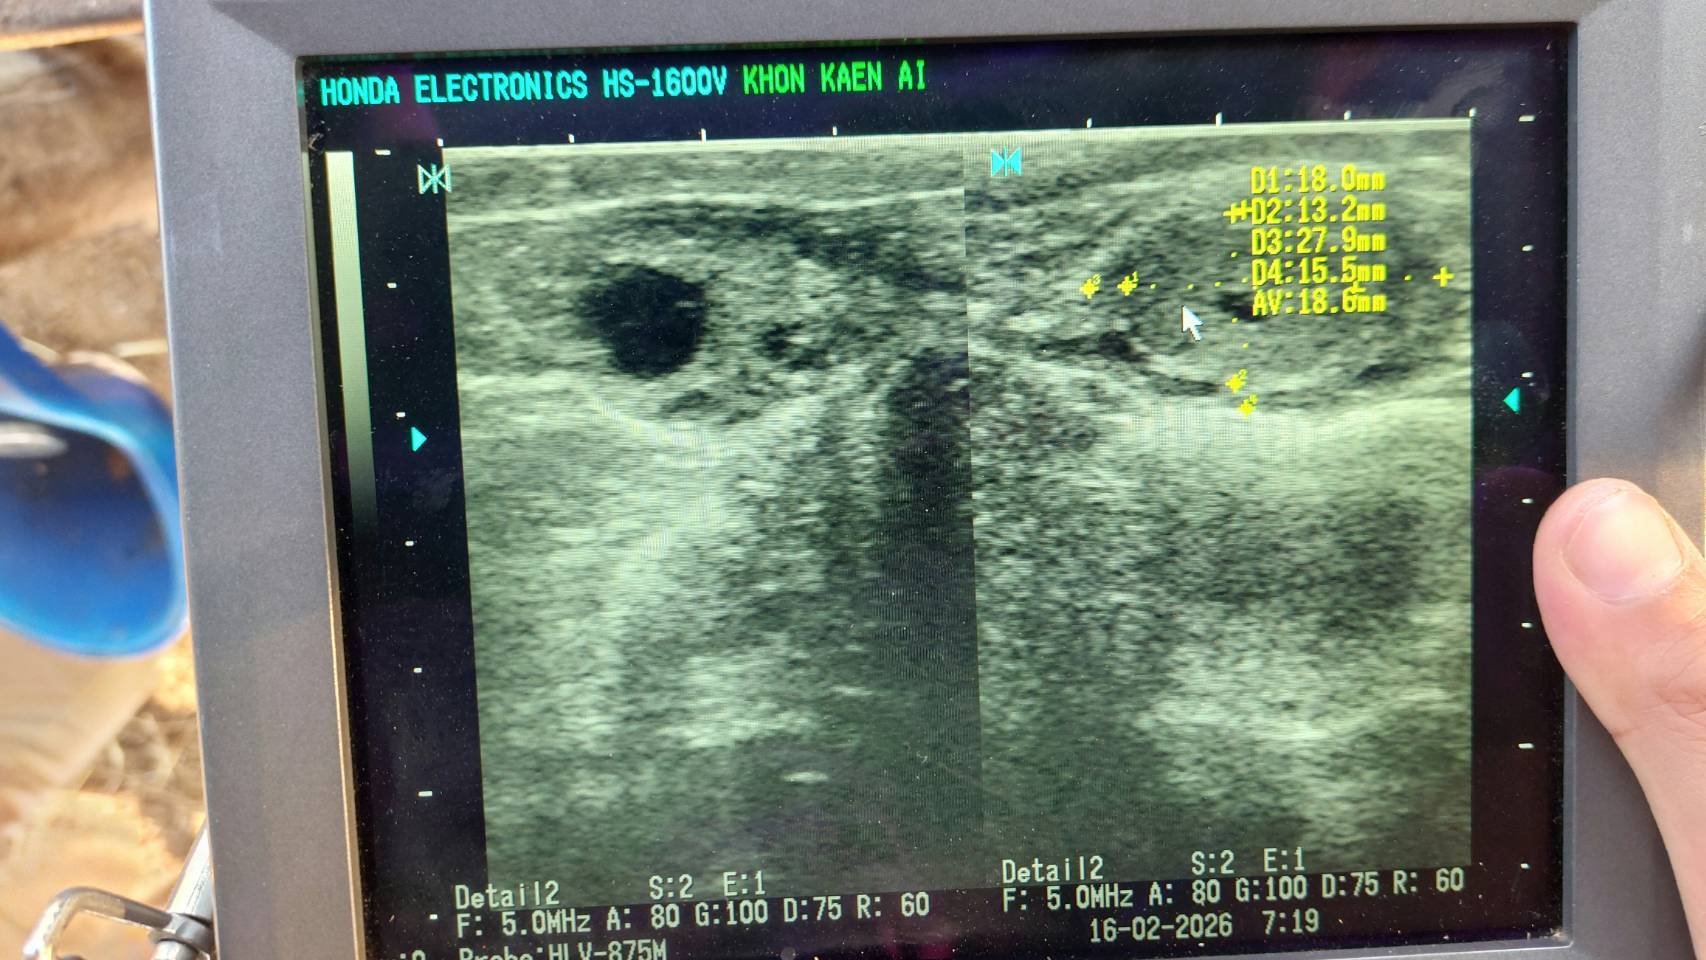

ศูนย์วิจัยการผสมเทียมและเทคโนโลยีชีวภาพขอนแก่น ปฏิบัติงานโครงการ “การยกระดับศักยภาพการผลิตเนื้อโคขุนระดับพรีเมียมด้วยโคพันธุ์ไทยแบล็คกรมปศุสัตว์” ในฟาร์มที่เข้าร่วมโครงการฯ ณ MP. ฟาร์ม ม.2 ต.บ้านค้อ อ.เมือง จ.ขอนแก่น ดังนี้ ตรวจโคตัวรับด้วย Ultrasound ก่อนย้ายฝาก, ย้ายฝากตัวอ่อนโคพันธุ์ไทยแบล็ค, ฉีดฮอร์โมน PGF2⍺ และฉีดวิตามิน AD3E